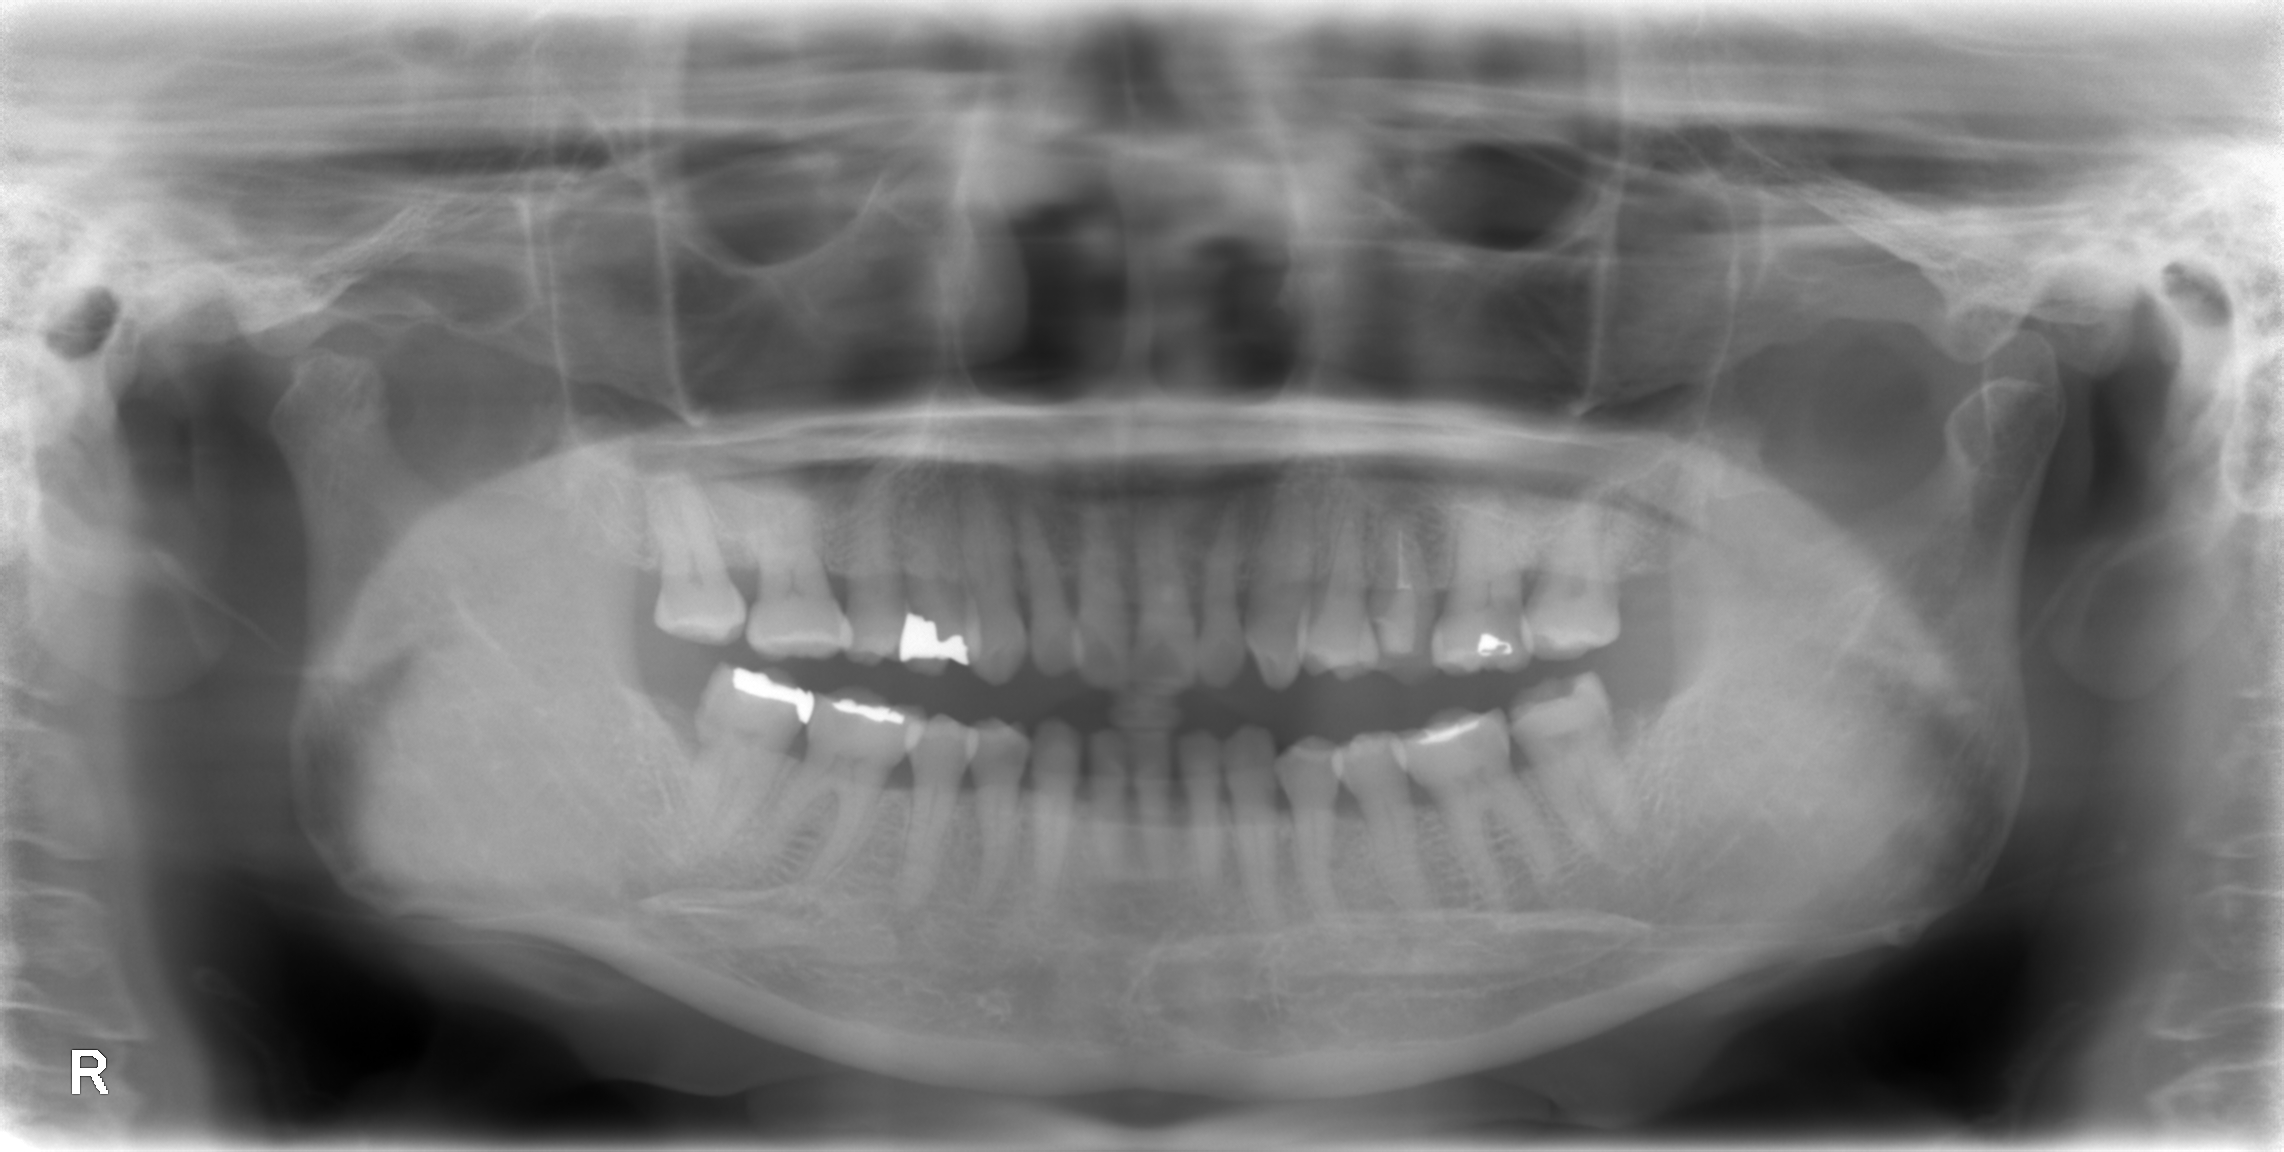

患者さんにいただいたレントゲンは以下である。

画質の悪いパノラマ写真だ。

これで根管の何を判断できるというのだろうか?

私には皆目見当がつかない。

ヨシダ社のパノラマと前述のパノラマを比較してほしい。

話にならないくらい、どちらが優れた画質であるか?ということを。